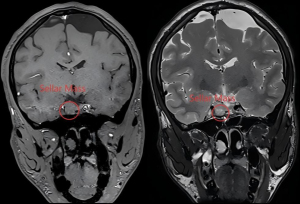

The patient returned to our hospital on June 27, 2023. A physical examination revealed several distinct features, including a prominent eyebrow arch, a large nose, thick lips, an enlarged tongue, an absence of toothcomb and backbites, enlarged joints in both hands, a shoe size of 42, and an enlarged toe joint. MRI (Figure 2) showed postoperative changes in sellar region occupation, right sellar nodules, and residual glands.